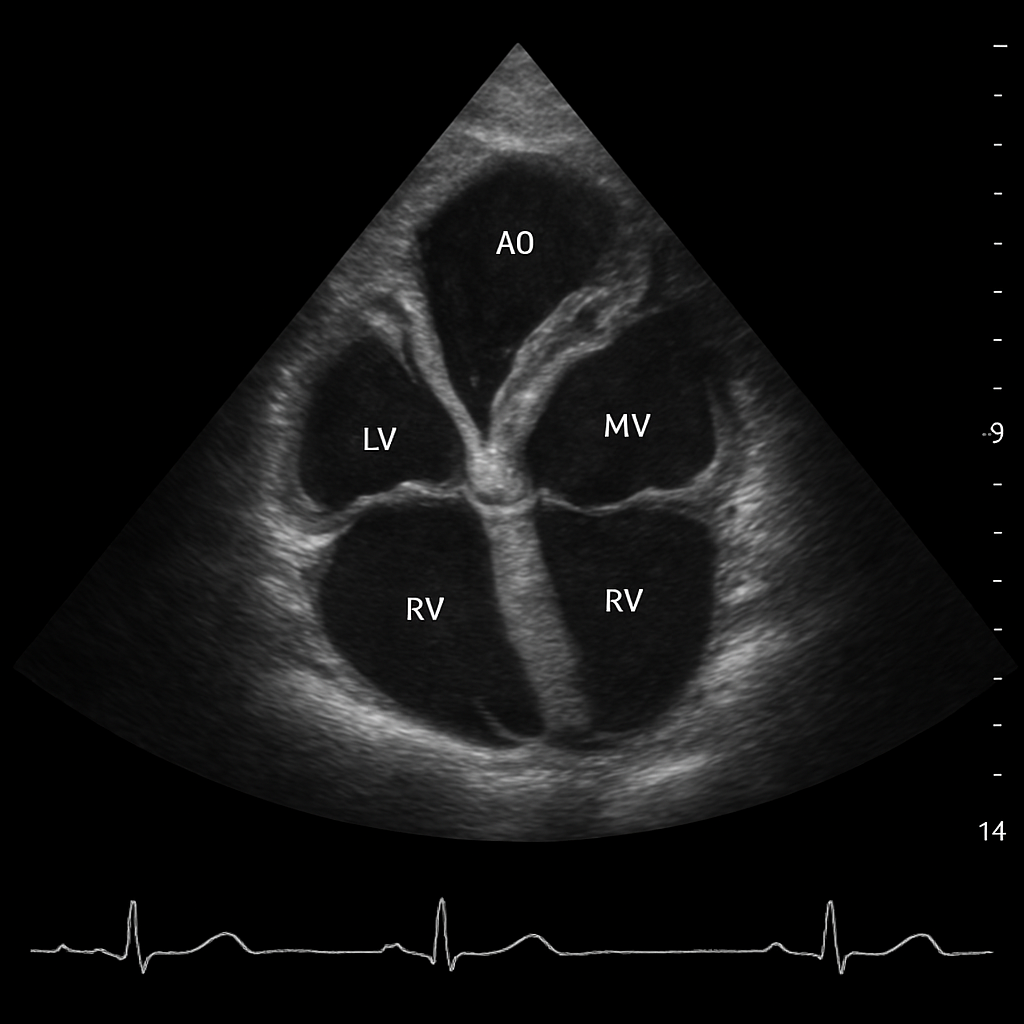

Echo — Apical Four-Chamber

Transthoracic echocardiogram apical four-chamber (A4C) view showing all four cardiac chambers, mitral and tricuspid valves, and interatrial and interventricular septa.

ULTRASOUND AI Generated 2026-03-16

Apical Four Chamber

2D B-mode TTE, apical 4-chamber. Apex at top of sector. All four chambers visible. ECG trace at bottom.

OpenAI gpt-image-1